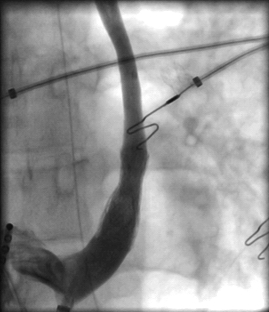

A 19-year-old female underwent repair of complex congenital heart disease (atrial and ventricular septal defect with a criss-cross atrioventricular relationship) in infancy. Because or recurrent palpitations she underwent an electrophysiology study. Atypical atrioventricular nodal reentrant tachycardia was diagnosed. Catheter ablation was performed successfully using cryothermal energy. The diagnostic and therapeutic approach is discussed.